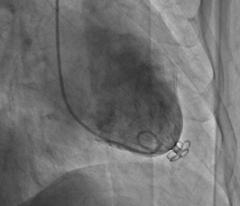

“经皮心室重建术”是针对急性心肌梗死患者易发的心力衰竭的陈旧前壁心肌梗死伴心力衰竭患者的新的治疗方法。这类患者常因本身病情危重而无法承受外科手术治疗。“经皮心室重建术”基于国外最新研发的一种新的器械,该器械是一个左(心)室隔离装置,形似“降落伞”,采用微创介入的方法,经股动脉置入到左室心尖部,将异常收缩的室壁隔离开,从而减少左室容积,改善心力衰竭患者临床症状及心功能。该项技术最早报道于2007年,近年来在国外逐渐开展,积累了上百例的经验,并获得欧洲CE认证。

北大医院心内科经过周密的术前准备,由霍勇教授、洪涛教授分别为两名患者成功地将“降落伞”-左室隔离装置放置到患者心室中,减少患者心脏的容积,有效改善心力衰竭的临床症状。目前两名患者恢复良好。